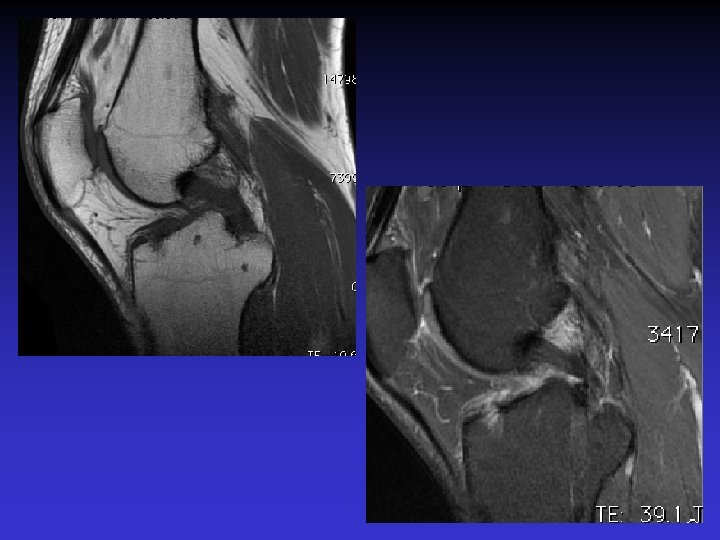

• • • Pas d’épanchement Pas de lésion méniscale Pas de lésion cartilagineuse Pas de lésion osseuse Anomalies du LCA • Épaissi • Hyper signal T 1 et T 2 • Orientation des fibres conservée • Kyste

ASPECT IRM • • Hyposignal TI Hypersignal T 2 Pas de prise du contraste après Gado IV Continuité conservée du LCA+++ avec dilacération des fibres • Aspect en « tige de céleri »

RUPTURE DU LCA